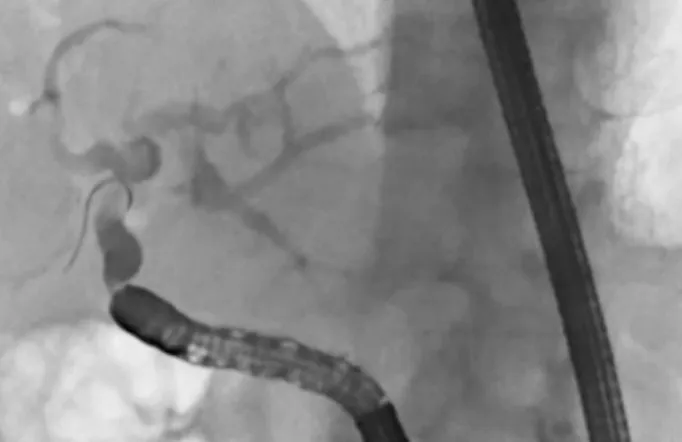

ERCP関連手技ERCP-related procedures

• バルーン内視鏡ガイド下内視鏡的逆行性胆管膵管造影(BE-ERCP)

• 術後困難症例に対するBE-ERCPによる胆道ドレナージ

胆膵部門の特徴の1つとして膵がん早期発見の試みがあります。膵がんは固形がんの中で予後最悪と言われていますが、直径10mmまでのサイズで発見できた場合には5年生存率(5年生きられる確率)が90%以上と最新のデータで発表されています。これらを見つけることは通常の画像診断では難しく、早期膵がんに特殊な所見を発見する必要があります。特殊な所見とは小さながんが存在することによって起きてくる間接的な画像所見を指し、・主膵管拡張/狭窄・分枝膵管拡張・膵実質限局性萎縮・膵管周囲低エコー等があります(画像はSagami R et al. Cancers 2021より引用)。

これらは全てStage 0の膵がんの方の画像所見であり、通常のCTやMRIでも確認できる他、EUSを用いてより詳細に発見することもできます。これまでに多数の早期膵がんを診断・治療した実績は世界的にも認められており、大分の患者さまにも良質な診断・治療を受けて頂くことが出来ます。